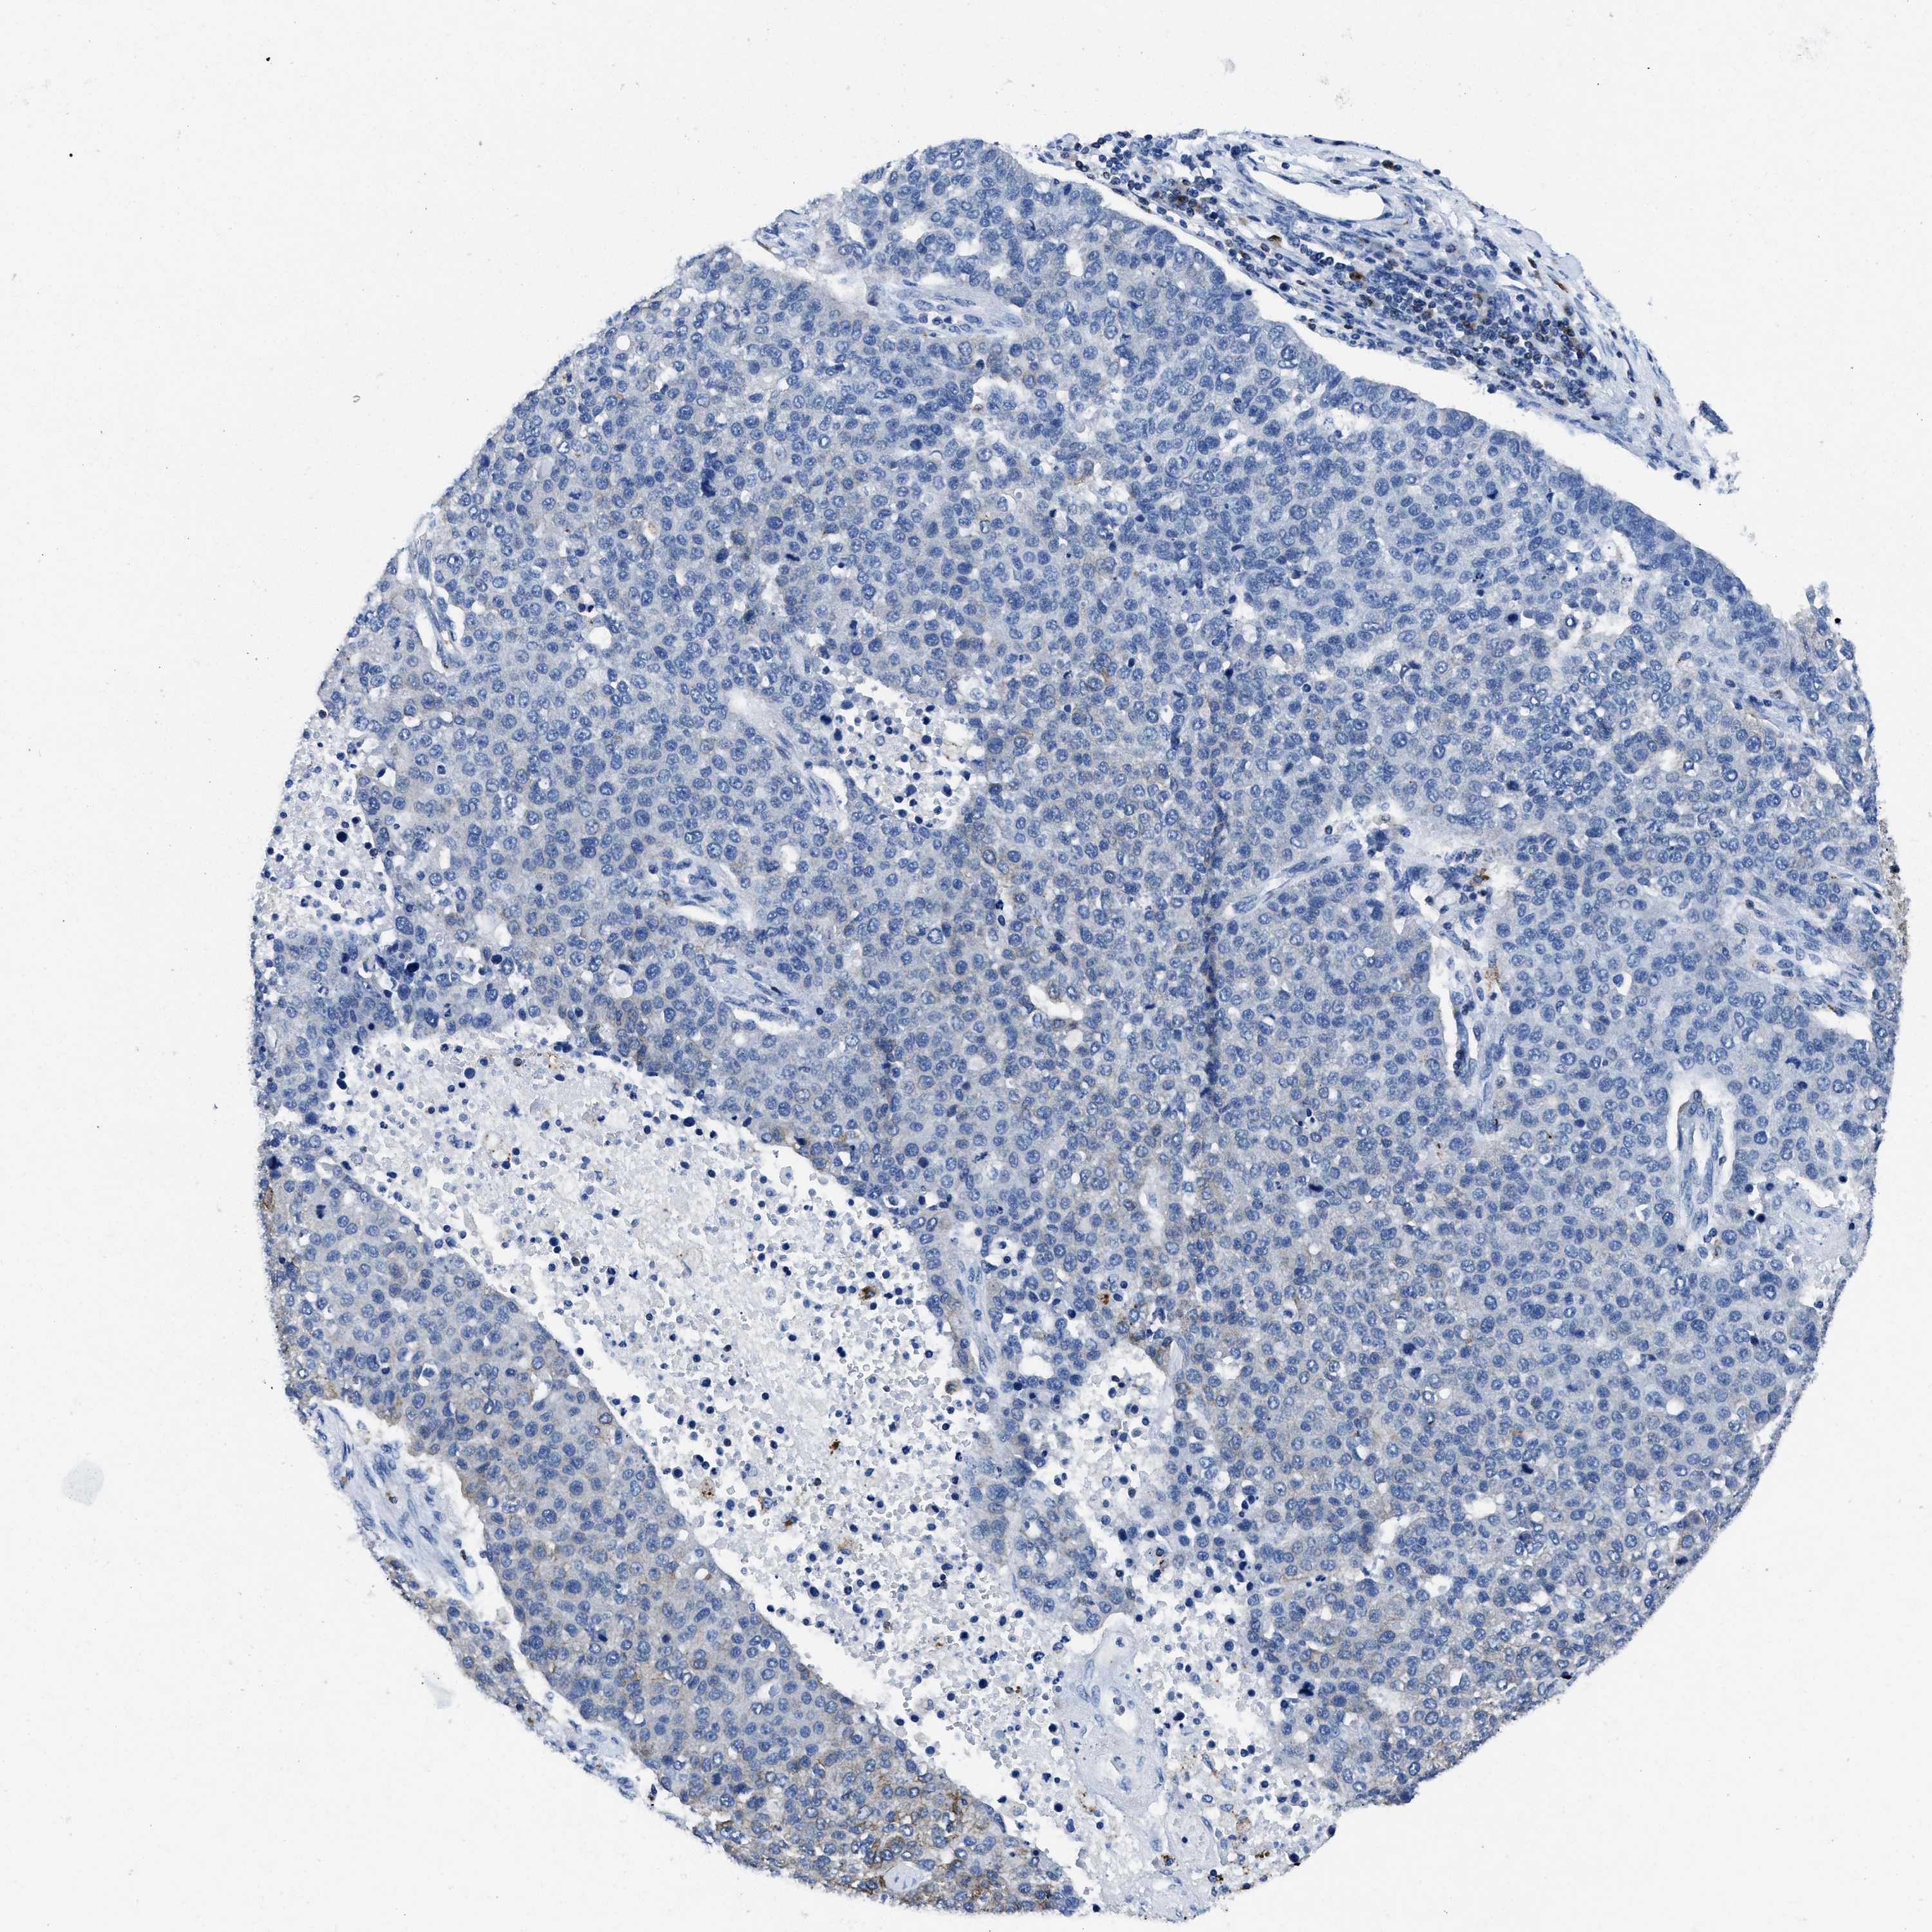

PANCREATIC CANCER - Protein expressioni

A mouse-over function shows sample information and annotation data. Click on an image to view it in a full screen mode. Samples can be filtered based on level of antibody staining by selecting one or several of the following categories: high, medium, low and not detected. The assay and annotation is described here.

Note that samples used for immunohistochemistry by the Human Protein Atlas do not correspond to samples in the TCGA dataset.

Antibody stainingi

Antibody staining in the annotated cell types in the current human tissue is reported as not detected, low, medium, or high, based on conventional immunohistochemistry profiling in selected tissues. This score is based on the combination of the staining intensity and fraction of stained cells.

Each image is clickable and will lead to virtual microscopy that enables deeper exploration of all samples and also displays staining intensity scores, fraction scores and subcellular localization as well as patient and tissue information for each sample.

Antibody HPA008572

Antibody CAB018594

Staining

High

Medium

Low

Not detected

Intensity

Strong

Moderate

Weak

Negative

Quantity

>75%

75%-25%

<25%

None

Location

Nuclear

Cytoplasmic/membranous

Cytoplasmic/membranous,nuclear

Adenocarcinoma, NOS